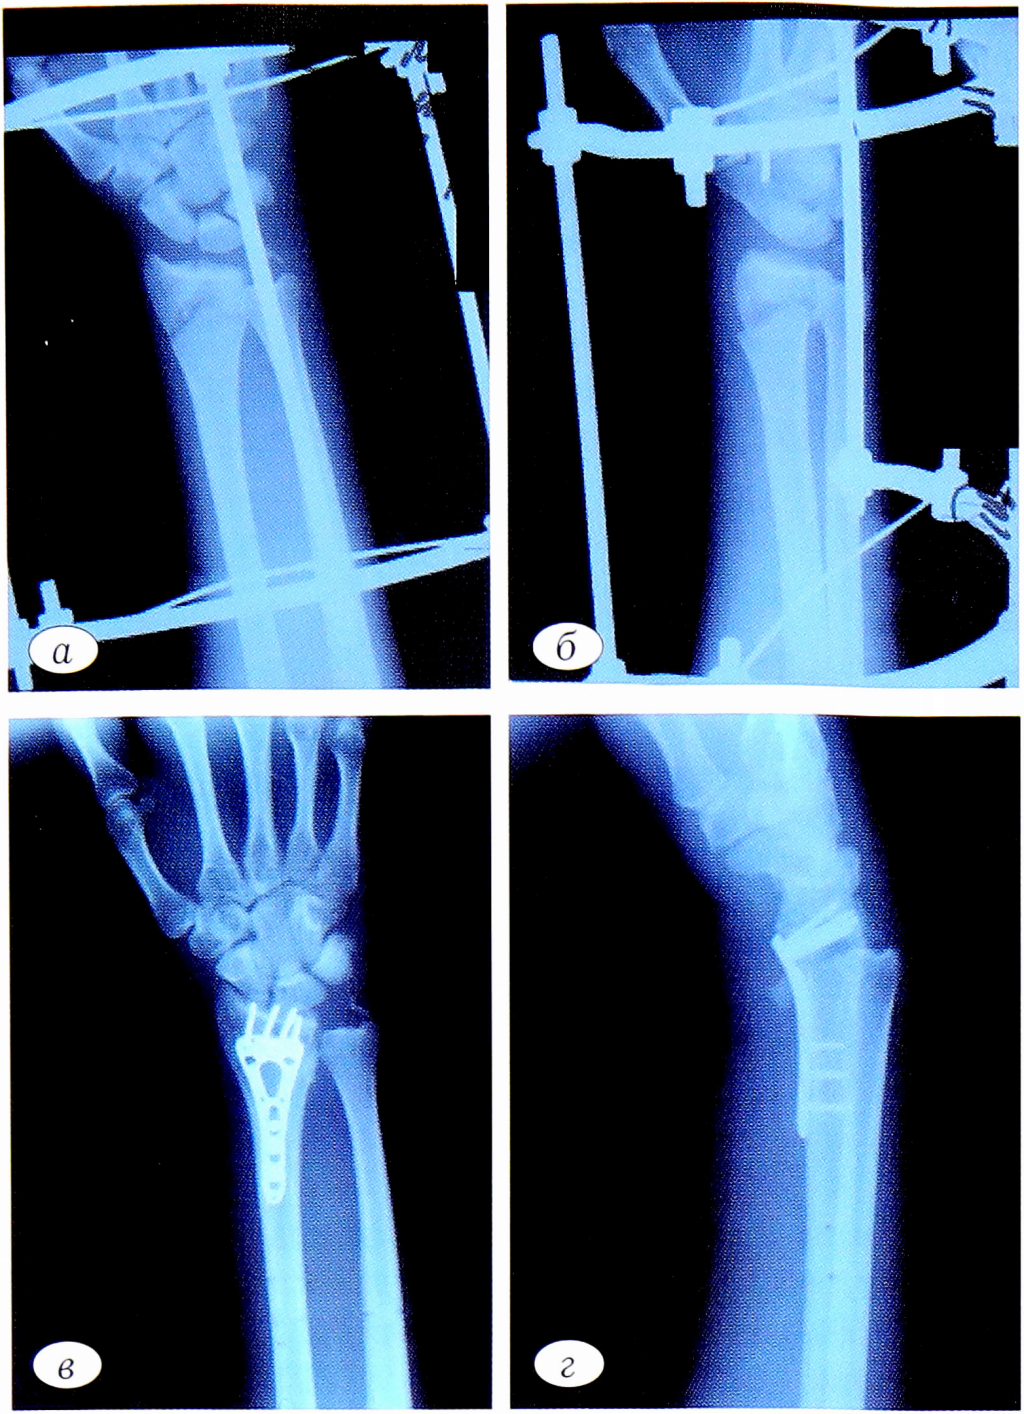

В тот же день были выполнены установка дистракционного аппарата Коршунова—Лазарева (рис. 1, а, б), остеосинтез левого бедра интрамедуллярным стержнем. Спустя 6 сут после стабилизации состояния пациента была выполнена операция — конверсия дистракционного аппарата, накостный остеосинтез пластиной LCP-VA («Synthes») (см. рис. 1, в, г).

Рис. 1. Рентгенограммы левого предплечья пациента П. а — внутрисуставной оскольчатый перелом дистального метаэпифиза лучевой кости, перелом шиловидного отростка локтевой кости. После установки дистракционного аппарата Коршунова—Лазарева (прямая проекция); б — боковая проекция (смещение отломков в аксиальной плоскости). Контрольные рентгенограммы левого предплечья после остеосинтеза пластиной через 6 сут: в — прямая проекция; г — боковая проекция.

Fig. 1. X-rays of patient P.’s left forearm. a — intra-articular comminuted fracture of the distal lUBtipifica of the radius, fracture of the styloid process; ulna. After installation of the distraction apparatus Korshunov— Lazarev (direct projection); b — side projection (displacement of fragments in the axial plane); c — controlling x-rays of the left forearm after oleosinBtesa plate after 6 days: in direct projection; d — BokofflWai projection.

Рис. 2. Контрольные рентгенограммы спустя 12 мес с момента выполнения оперативного лечения. а — прямая проекция; б — боковая проекция.

Fig. 2. Control radiographs after 12 months from the moment of surgical treatment. a — direct projection; b — lateral projection.